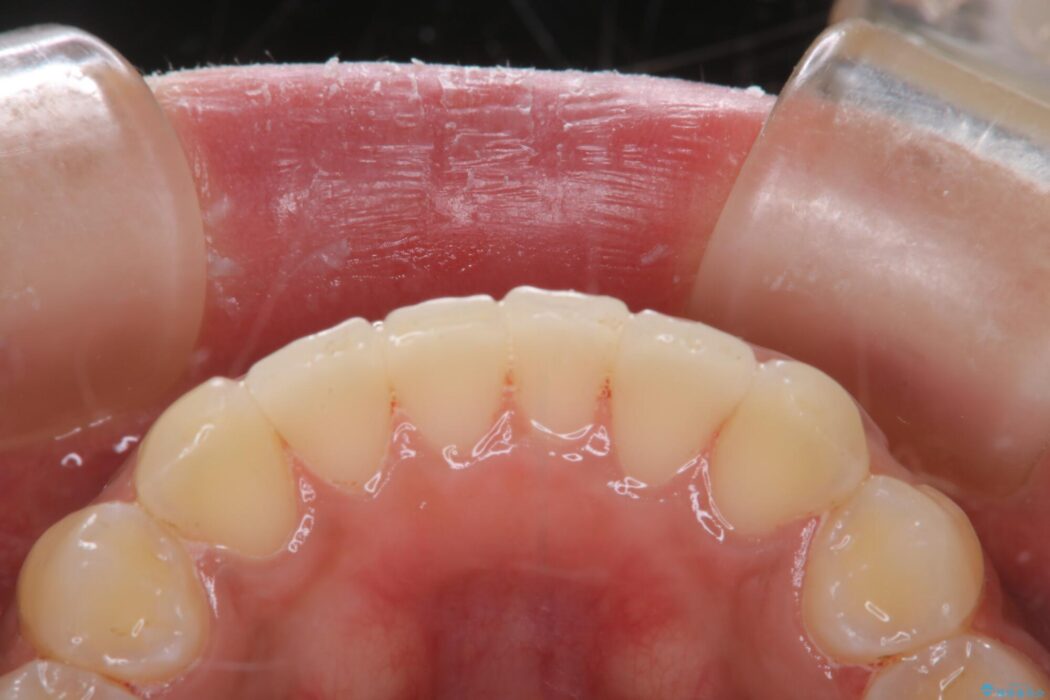

【20代女性】タバコのヤニ(ニコチン、タール)を徹底的に除去

タバコによって付着したステインを綺麗にしたいとのことで来院されました。

ステインがこびりついていたため、PMTC60分コースを行いました。

治療後について

タバコに含まれているタールが歯の黄ばみの原因になります。その黄ばみなどを、無理に落とそうとしたりすると歯の表面に傷がついてしまったり余計に汚れがつきやすい状態になることがあります。

PMTCでは、専門の機材を使用し、歯の表面の凸凹にミネラルを補給して、ツルツルの表面に仕上げます。定期的にPMTCを行うことにより、歯質の強化になり着色がつきにくい状態になります。